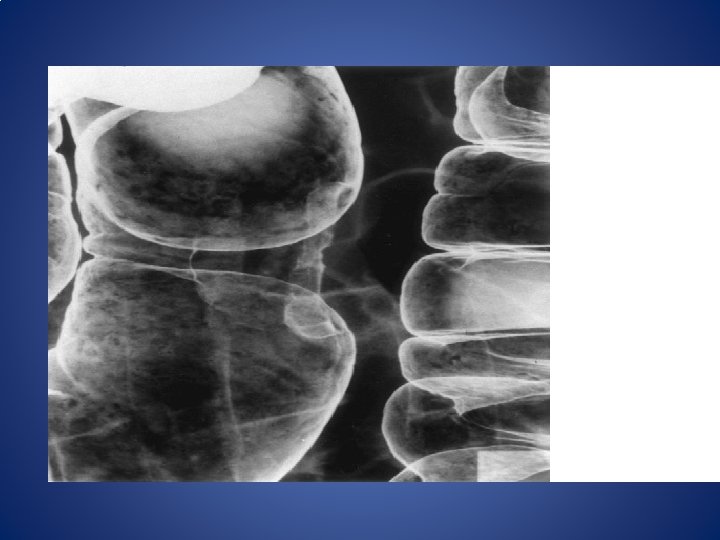

PATHOLOGY #HISTOLOGICALLY • Adenocarcinoma #GROSS • Ulcerative • Papilliferous • Infilterative • Annular

Gross specimen of resected rectal ca